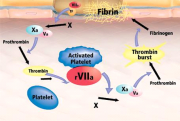

| 16:06, 4 בנובמבר 2012 | נובוסבן1.png (קובץ) |  |

97 קילו־בייטים | Motyk | 1 | |